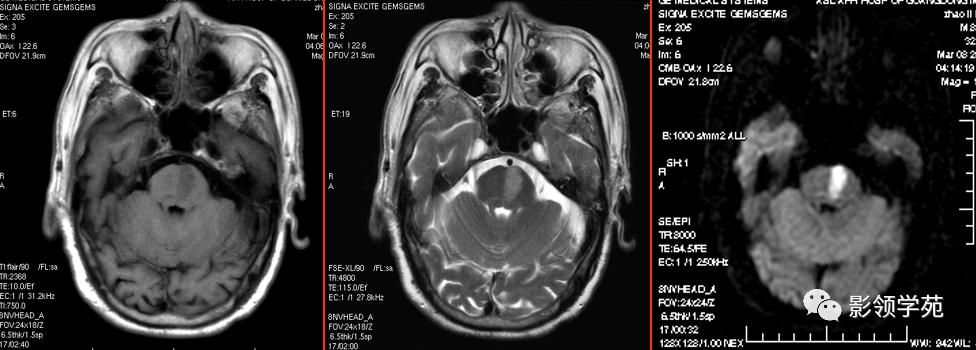

亚急性中期 :正铁血红蛋白(红细胞溶解)  T1WI高信号,T2WI上逐渐从周边向中心高信号

图片

亚急性后期 :血肿周边含铁血黄素 ,T2WI为低信号,中心T1WI与T2WI均为高信号